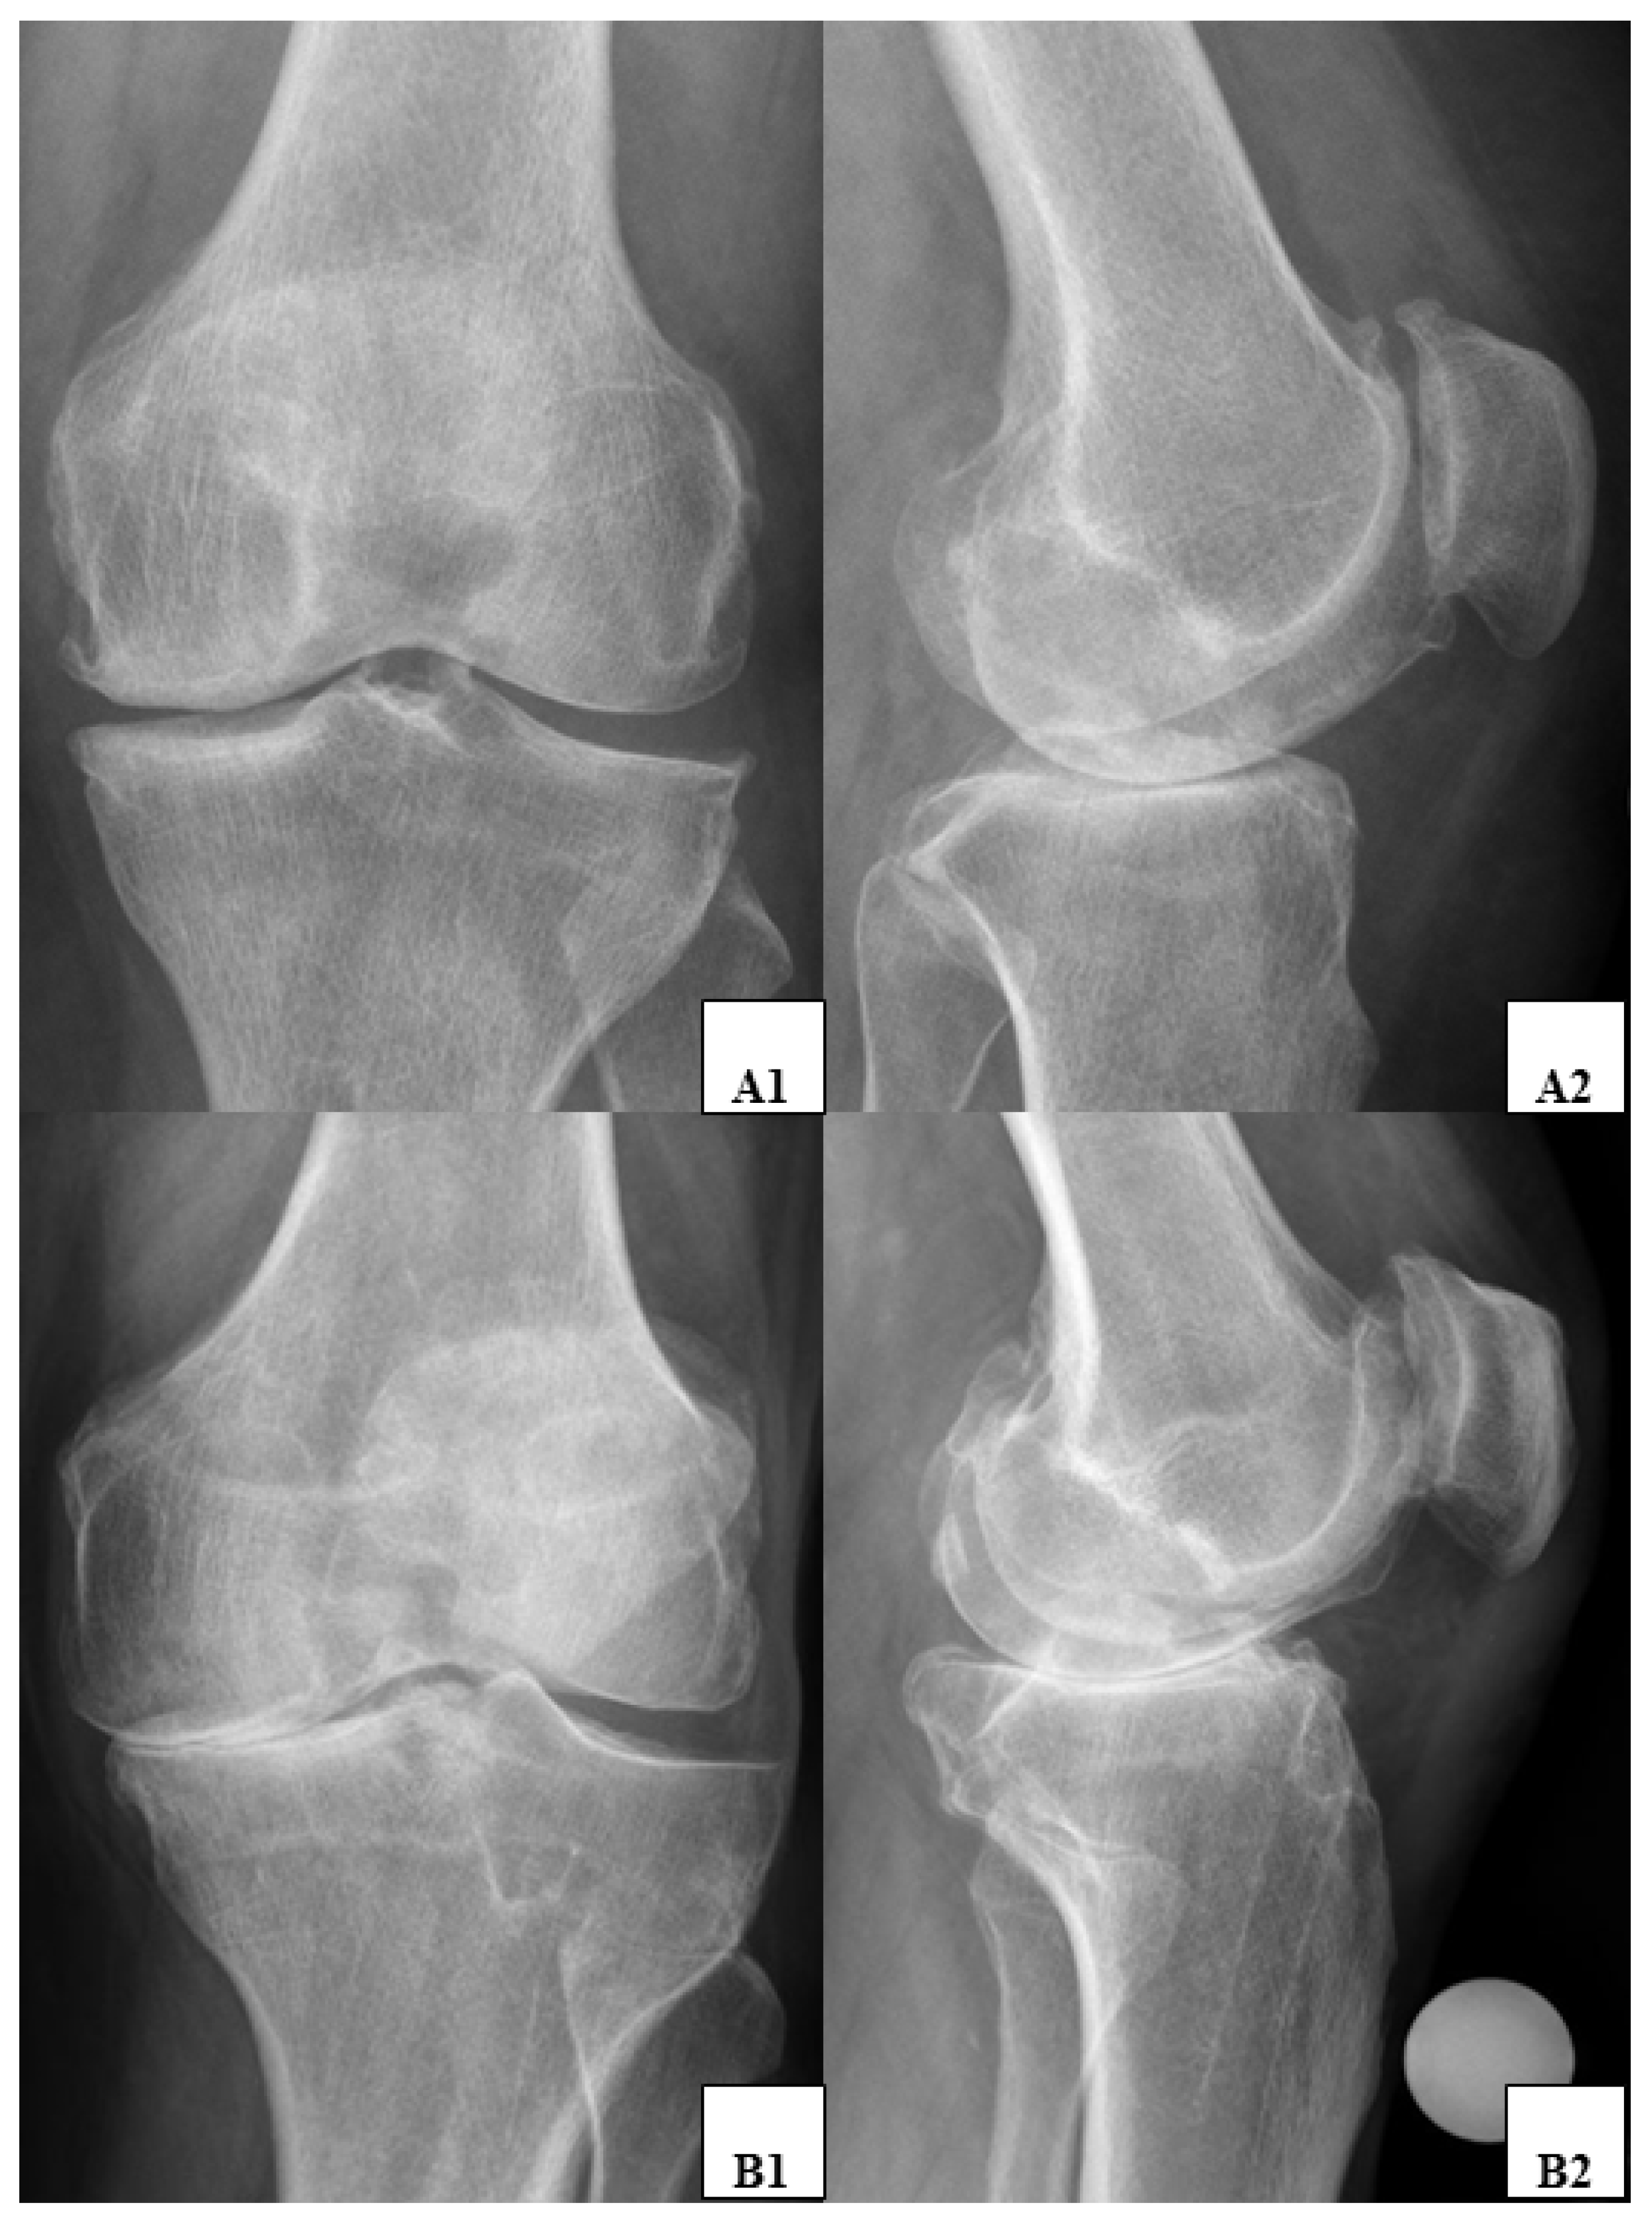

2.3. Radiographic Parameters and Analysis